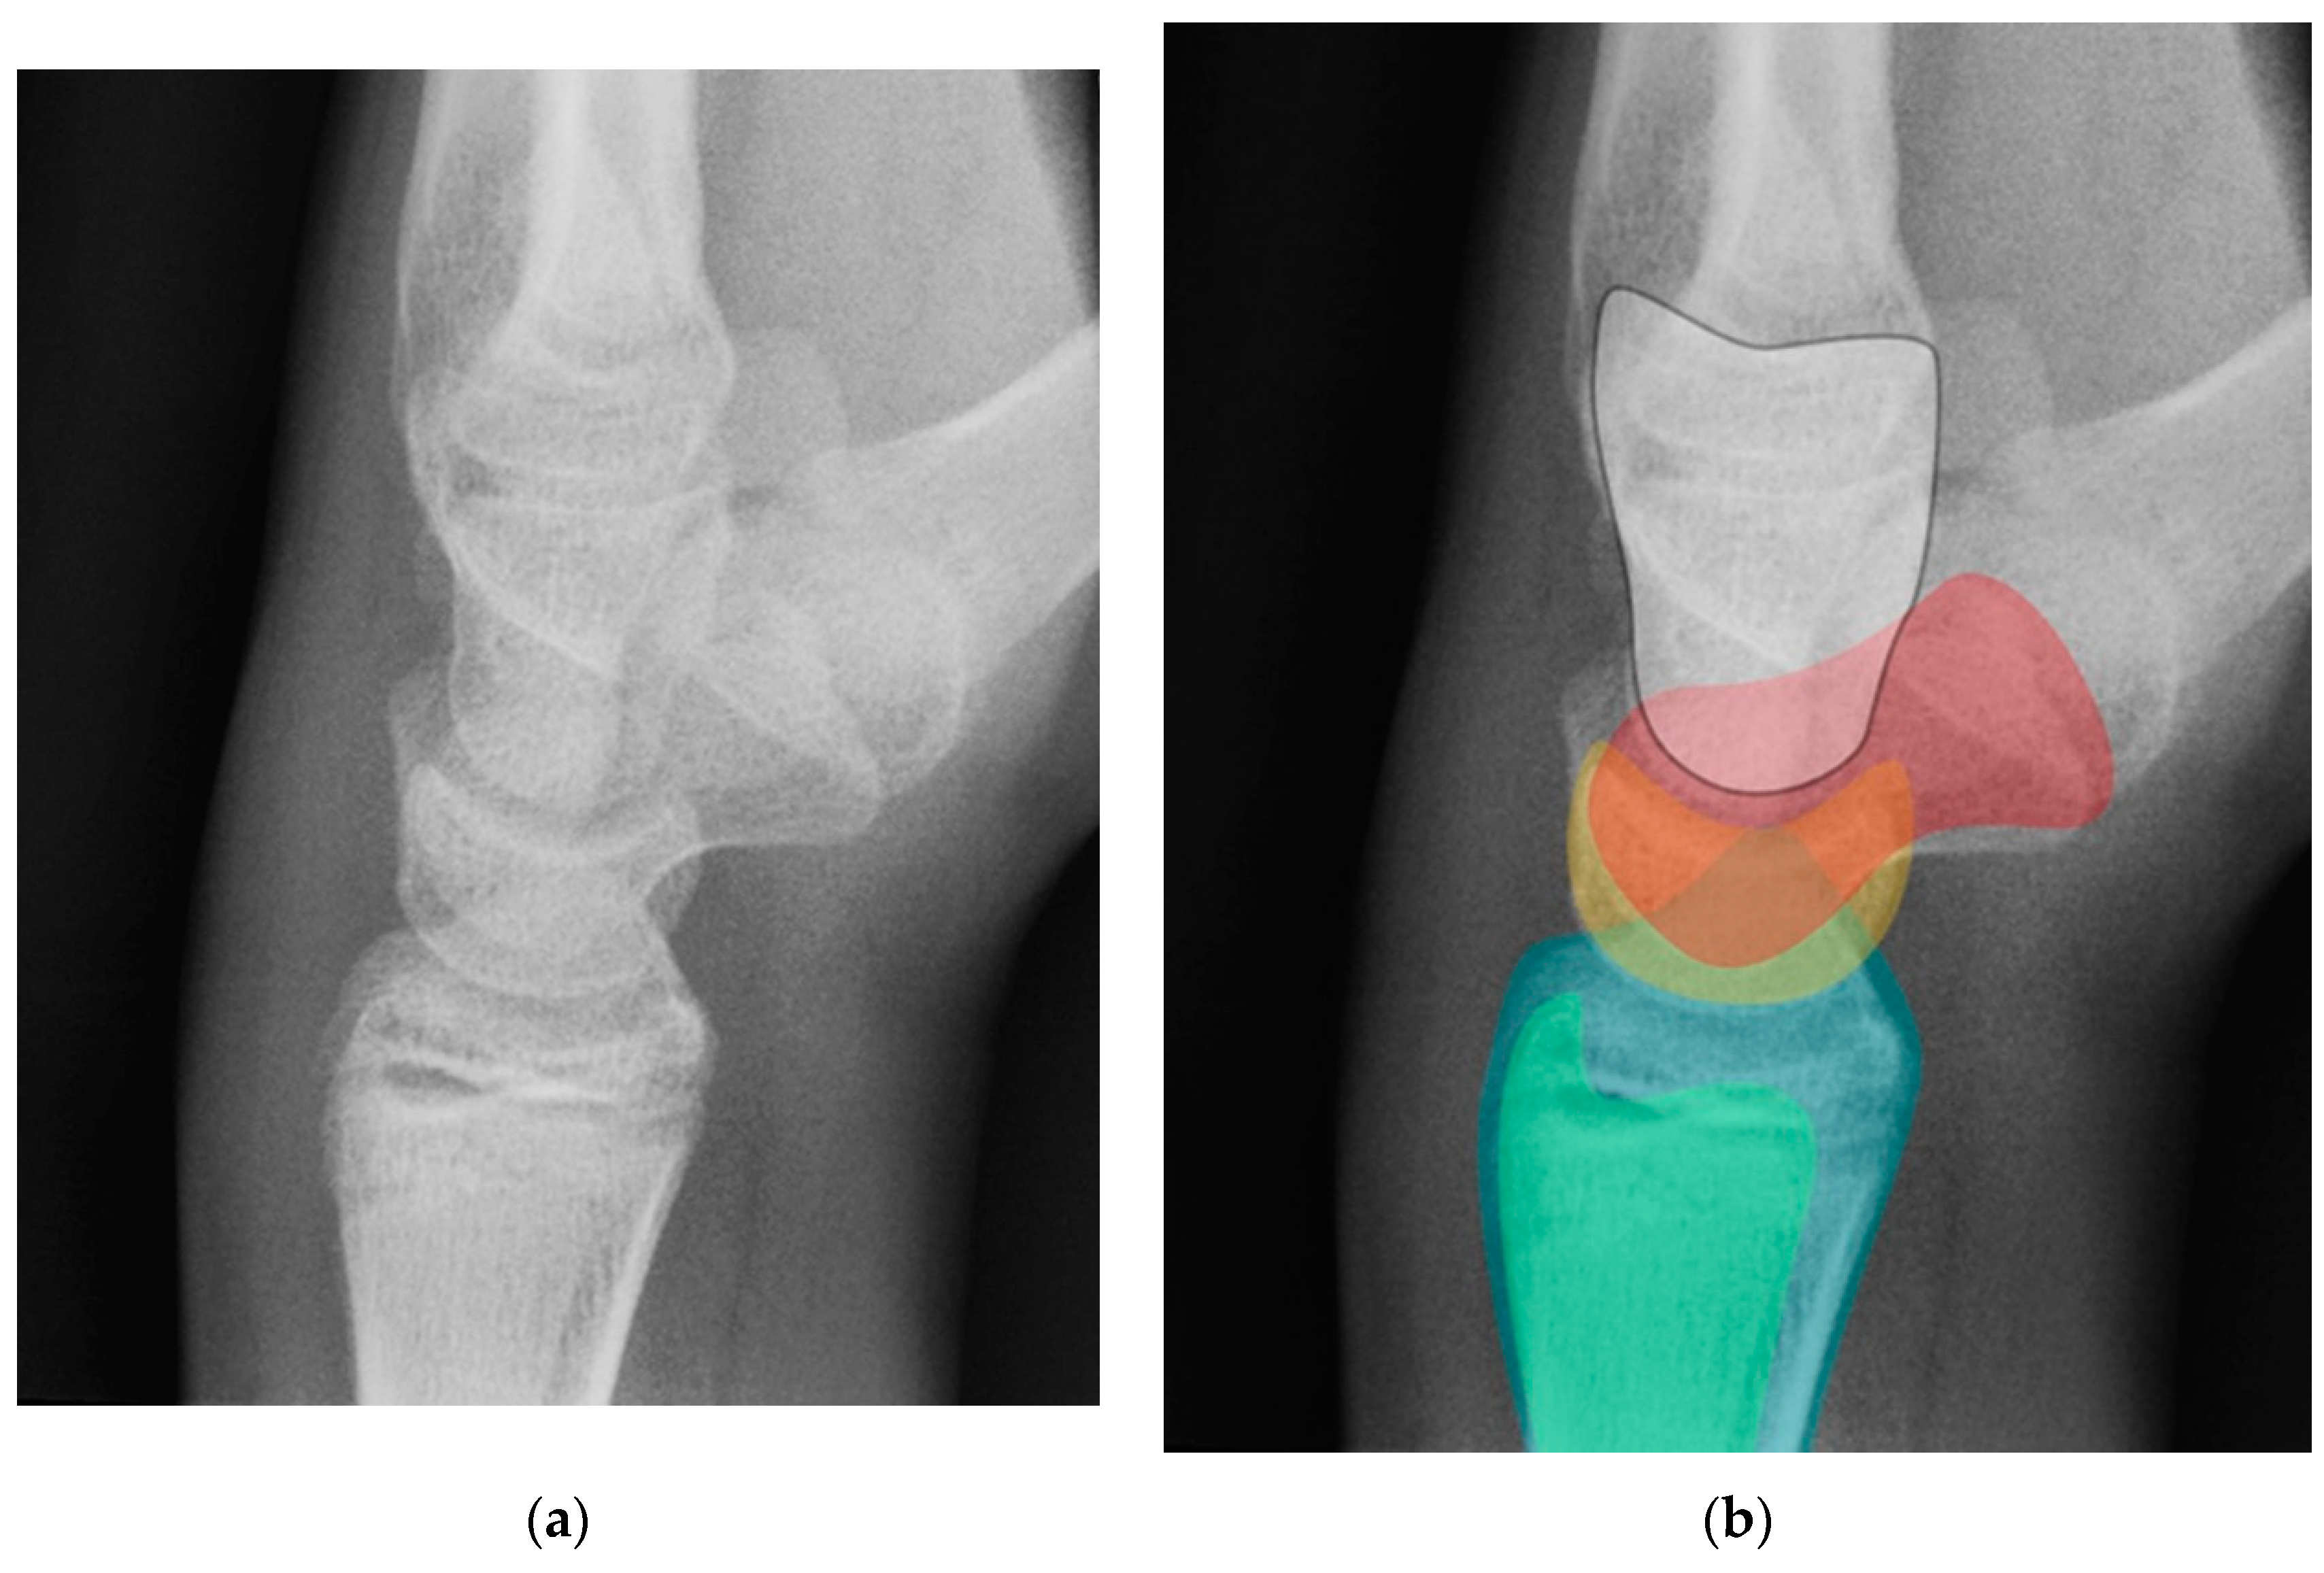

Figure 18. (a) Neutral lateral view wrist radiograph showing normal anatomy; (b) Radiograph overlay depicting its constituent anatomy; Green – ulna, Blue – radius, Yellow – lunate, Red – scaphoid, White – capitate.